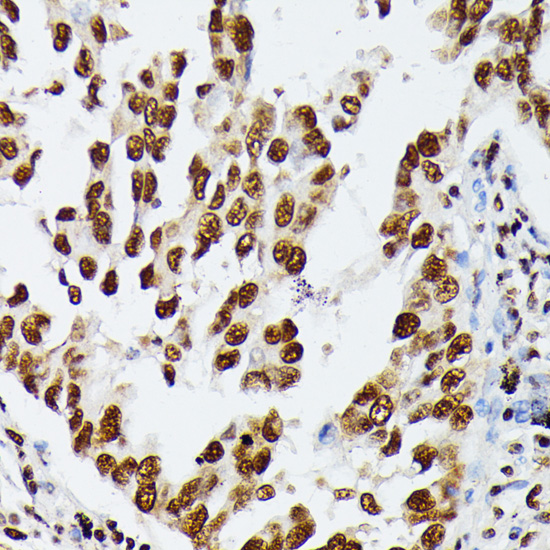

Immunohistochemistry of paraffin-embedded rat liver using HNRNPD at dilution of 1:100 (40x lens).

Immunohistochemistry of paraffin-embedded human lung cancer using HNRNPD at dilution of 1:100 (40x lens).

Immunohistochemistry of paraffin-embedded mouse brain using HNRNPD at dilution of 1:100 (40x lens).